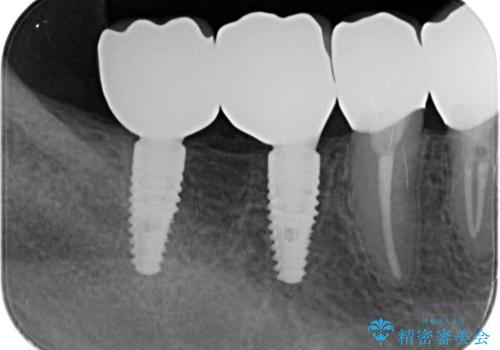

検査の結果、残すことの難しい歯をインプラントに置き換え、残すことのできる歯は虫歯の徹底的な除去後にセラミック治療を行っていくこととしました。

- 125万円(インプラント×2・チタンカスタムアバットメント×2・ジルコニアクラウン×4・仮歯×4)費用は治療当時の料金となります

銀歯が口腔内からなくなり審美的になっただけでなく、歯ブラシのしやすさや噛み合わせの安定、口臭の減少など、良好な結果を得ることができました。